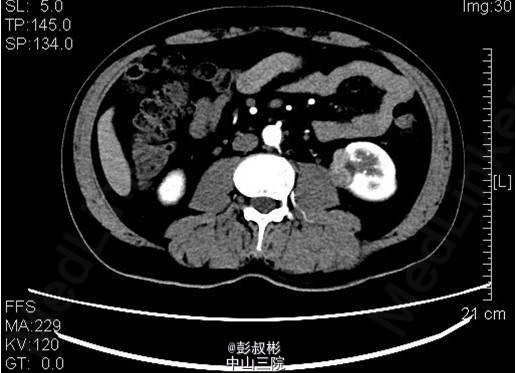

3、既往病史:高血压,高尿酸,高血脂6年,2013年行“右输尿管结石碎石取石术” 4、入院查体:未见明显异常体征。 5、影像学检查:中下腹部CT平扫+增强+CTU:左肾中盏可见结节状高密度影,直径约为6mm,基本同前。左肾下部可见大小约为36×21×23mm稍高密度影突出于包膜生长,较前明显增大,凸向肾外生长,浅分叶,其内见脂肪密度影,增强扫描可见轻度强化,病灶与左侧腰大肌关系密切。